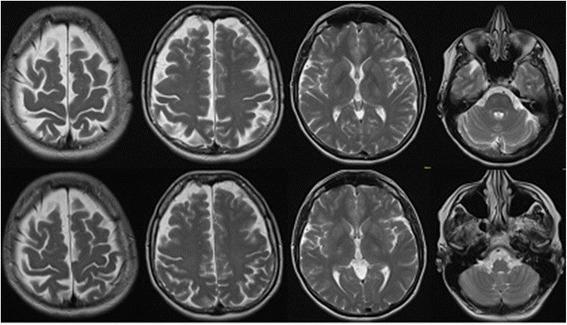

We present the case of a 50-year-old woman who developed a first-onset depressive syndrome with predominant cognitive impairment and inability to work. Antidepressive treatment and cognitive behavioral therapy over two years were unsuccessful. Neurological examination was unremarkable. Serum analysis showed increased thyroid peroxidase and thyroglobulin antibodies. Cerebrospinal fluid protein and albumin quotient were increased. Magnetic resonance imaging depicted unspecific, supratentorial white matter lesions and frontal accentuated brain atrophy. Electroencephalography was normal. Neuropsychological testing for attentional performance was below average. High-dose intravenous treatment with methylprednisolone over 5 days and oral dose reduction over 3 weeks led to the sustained improvement of clinical symptoms. Following discharge from the hospital, the patient returned to work, and 6.5 months after the start of therapy, no neuropsychological deficit remained.

我们报告一例50岁女性,首次出现以认知障碍为主且无法工作的抑郁综合征。两年的抗抑郁治疗和认知行为疗法均未成功。神经系统检查无异常。血清分析显示甲状腺过氧化物酶和甲状腺球蛋白抗体升高。脑脊液蛋白和白蛋白商数升高。磁共振成像显示非特异性幕上白质病变和额叶明显脑萎缩。脑电图正常。注意力表现的神经心理学测试低于平均水平。5天的大剂量静脉注射甲泼尼龙治疗及3周的口服剂量递减导致临床症状持续改善。出院后,患者恢复工作,治疗开始6.5个月后,神经心理学缺陷消失。